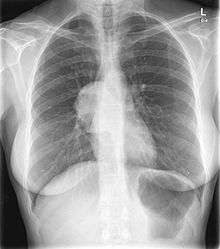

This PA chest radiograph demonstrates an abnormal contour in the right hilar region, with visualization of the pulmonary vessels through the mass (the hilar overlay sign) indicating its posterior mediastinal location. On resection this was found to be a benign solitary fibrous tumor of the pleura.